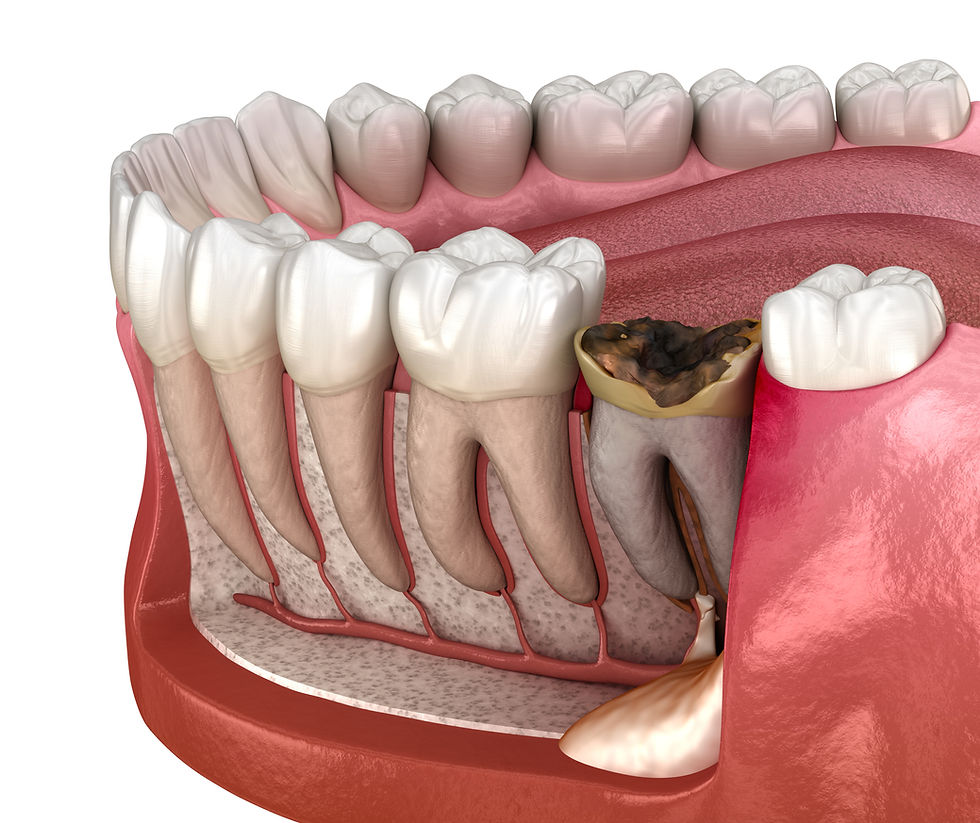

Retained root surgery removes tooth root fragments that remain in the jawbone after tooth extraction or breakage. These fragments can cause pain, infection, or interfere with healing and future dental work. Our minimally invasive techniques ensure complete removal and proper healing.

Retained root removal is a routine surgical procedure used to extract fragments of tooth roots left behind after a fracture or incomplete extraction. The process begins with diagnostic imaging to locate the root and assess its depth. Under local anaesthesia, your dentist will access the area, remove any bone if necessary, and extract the root using precise instruments. The site is then cleaned, sutured, and allowed to heal. This straightforward treatment helps prevent infection, restores oral health, and prepares the area for future procedures such as dental implants. With modern techniques, most patients find the experience comfortable and recovery uncomplicated.